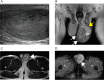

Case presentation: A 51-year-old Japanese male visited our hospital complaining of asymptomatic left scrotal swelling. Physical examination revealed a nontender elastic paratesticular mass (5.5 cm in diameter). Although testicular germ cell tumor was ruled out clinically, the possibility of malignant potential remained for the tumor. Since the patient consented to complete resection, a transinguinal radical orchiectomy was performed. The pathological diagnosis revealed cellular angiofibroma. The patient recovered without perioperative complications, and no apparent recurrence was observed at 5 years after surgery.